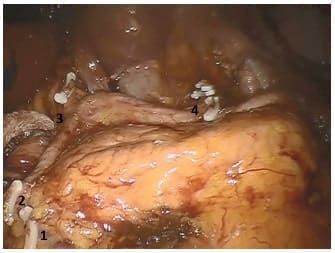

La arteria gástrica izquierda se seccionó en la raíz, luego de disecar el tejido linfático y el tejido graso en forma circunferencial, resecando los ganglios de la estación No 7, completando así el vaciamiento supra pancreático (figura 1).

Figura 1. Vaciamiento suprapancreático finalizado. 1. Muñón de vena gastroepiplóica derecha. 2. Muñón de arteria gastroepiplóica derecha. 3. Muñón de arteria gástrica derecha. 4. Muñón de vasos gástricos izquierdos.